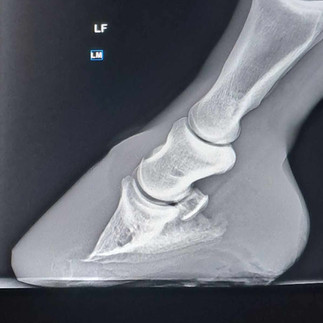

Bart Lambert's case involved a horse that had severe movement challenges due to an improper hoof angle, as confirmed by x-ray imaging. This situation needed a well-planned intervention to enhance the horse's comfort and mobility. Glushu was chosen for this task because it offers a strong and flexible solution that molds to each hoof's unique shape. Adding a wedge was crucial in this situation, as it helped to correct the hoof angle, allowing for more effective treatment of the underlying problems.

"Here we have another of my clients using Glushu glue on horse shoes. In the x-rays showed a poor angle. Due to this I had to build up a wedge prior to shoeing. Then I placed a Glushu and build a wedge on the shoe to de-rotate the foot. Before Glushu the horse was limping and walking very slow, post Glushu the horse is more in comfort and walking assuredly."